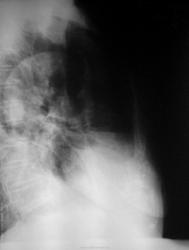

После плевральной пункции проведено контрольное рентгенологическое обследование.

Не могу разобраться, что за уровни жидкости на рентгенограммах при контрольном исследовании, возможно жидкость между плевральными спайками? Какова природа гидроторакса? Очень интересно ваше мнение…

3. правый бок

а на боковой если посмотреть в переднем отделе огк, это что за полость. а так тоже за зло, с метестазами

Мне тоже не ясно это за полость, вопрос с образованием решен, но что за уровни жидкости?

Развитие пневмогидроторакса после плевральной пункции, на фоне спаечного процесса?

Оно самое.